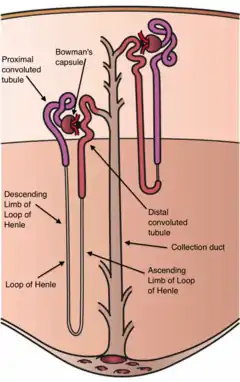

Diagram (left) of a long juxtamedullary nephron and (right) of a short cortical nephron. The left nephron is labelled with six named nephron segments. Also labelled is the collecting duct, mislabelled the "collection duct"; it is the last part of the nephron. | |

The interior of Bowman's capsule, called Bowman's space, collects the filtrate from the filtering capillaries of the glomerular tuft, which also contains mesangial cells supporting these capillaries. These components function as the filtration unit and make up the renal corpuscle. The filtering structure (glomerular filtration barrier) has three layers composed of endothelial cells, a basement membrane, and podocytes (foot processes). The tubule has five anatomically and functionally different parts: the proximal tubule, which has a convoluted section the proximal convoluted tubule followed by a straight section (proximal straight tubule); the loop of Henle, which has two parts, the descending loop of Henle ("descending loop") and the ascending loop of Henle ("ascending loop"); the distal convoluted tubule ("distal loop"); the connecting tubule, and the last part of nephron the collecting ducts. Nephrons have two lengths with different urine-concentrating capacities: long juxtamedullary nephrons and short cortical nephrons.

Length difference

Cortical nephrons (the majority of nephrons) start high in the cortex and have a short loop of Henle which does not penetrate deeply into the medulla. Cortical nephrons can be subdivided into superficial cortical nephrons and midcortical nephrons.[8]

Juxtamedullary nephrons start low in the cortex near the medulla and have a long loop of Henle which penetrates deeply into the renal medulla: only they have their loop of Henle surrounded by the vasa recta. These long loops of Henle and their associated vasa recta create a hyperosmolar gradient that allows for the generation of concentrated urine.[9] Also the hairpin bend penetrates up to the inner zone of medulla.[10]

Juxtamedullary nephrons are found only in birds and mammals, and have a specific location: medullary refers to the renal medulla, while juxta (Latin: near) refers to the relative position of the renal corpuscle of this nephron - near the medulla, but still in the cortex. In other words, a juxtamedullary nephron is a nephron whose renal corpuscle is near the medulla, and whose proximal convoluted tubule and its associated loop of Henle occur deeper in the medulla than the other type of nephron, the cortical nephron.

The juxtamedullary nephrons comprise only about 15% of the nephrons in the human kidney.[1]: 24 However, it is this type of nephron which is most often depicted in illustrations of nephrons.

In humans, cortical nephrons have their renal corpuscles in the outer two thirds of the cortex, whereas juxtamedullary nephrons have their corpuscles in the inner third of the cortex.[1]: 24